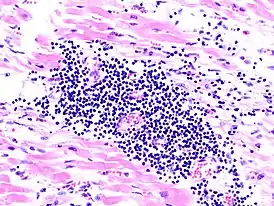

Эндомиокардиальной биопсии: В настоящее время считается, что диагноз «миокардит» может быть подтверждён только данными эндомиокардиальной биопсии, которая, однако, дает много ложноотрицательных и сомнительных результатов. При оценке результатов биопсии, как правило, используются Далласские диагностические критерии.

Миокардит считается определенным при наличии воспалительной клеточной инфильтрации (не менее 3—5 лимфоцитов в поле зрения светового микроскопа) и некроза или повреждения кардиомиоцитов. Выявление клеточной инфильтрации и неизмененных кардиомиоцитов соответствует сомнительному диагнозу. Данные повторной биопсии миокарда позволяют оценить динамику и исход процесса и говорить о продолжающемся, разрешающемся или разрешившемся миокардите. По количеству интерстициальных воспалительных клеток и их качественному составу, а также распространённости и тяжести деструктивных изменений кардиомиоцитов, наличию некротизированных кардиомиоцитов можно судить о степени остроты миокардита.